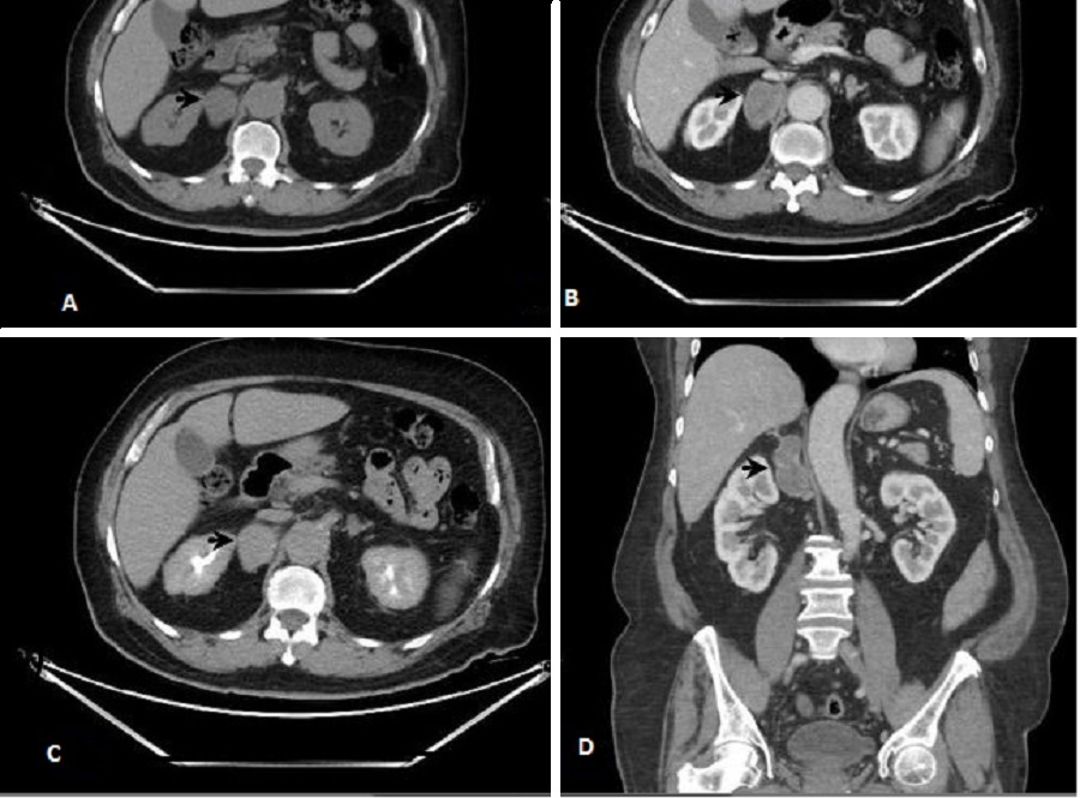

A follow-up CT scan showed a 4.2 x 3.5 x 6 cm heterogeneous right suprarenal mass with absolute washout of 40% and relative washout of 18.2%. Endocrine evaluation confirmed its nonfunctional nature. Due to tumor growth and malignancy concerns, a multidisciplinary team recommended surgical excision.

Figure 2 Figure 2 (A) Pre contrast phase; mass in right adrenal gland 30HU in non-contrast image; (B&D) mass enhancing to 55HU in porto venous phase; (C) persistent enhancement to 65HU in delayed phase